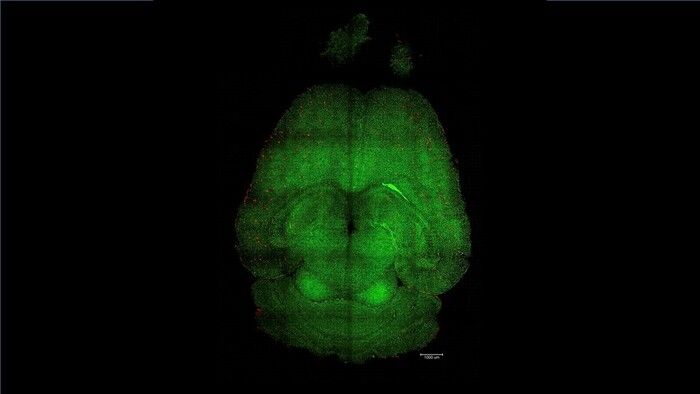

Il cervello umano contiene circa un miliardo di capillari, che svolgono un ruolo cruciale nel mantenimento della sua salute, ed è circondato dalla barriera emato-encefalica, il filtro che impedisce l'ingresso di sostanze pericolose come batteri o tossine.

I ricercatori coordinati dall'italiano Giuseppe Battaglia dell'Ibec hanno usato topi geneticamente modificati per produrre maggiori quantità della proteina beta-amiloide e sviluppare così un declino cognitivo simile a quello dell'Alzheimer, e gli hanno somministrato tre dosi di nanoparticelle . Dopo 6 mesi dal trattamento , un animale di 18 mesi, che equivalgono a circa 90 anni di un essere umano, aveva recuperato del tutto il comportamento di un topo sano.